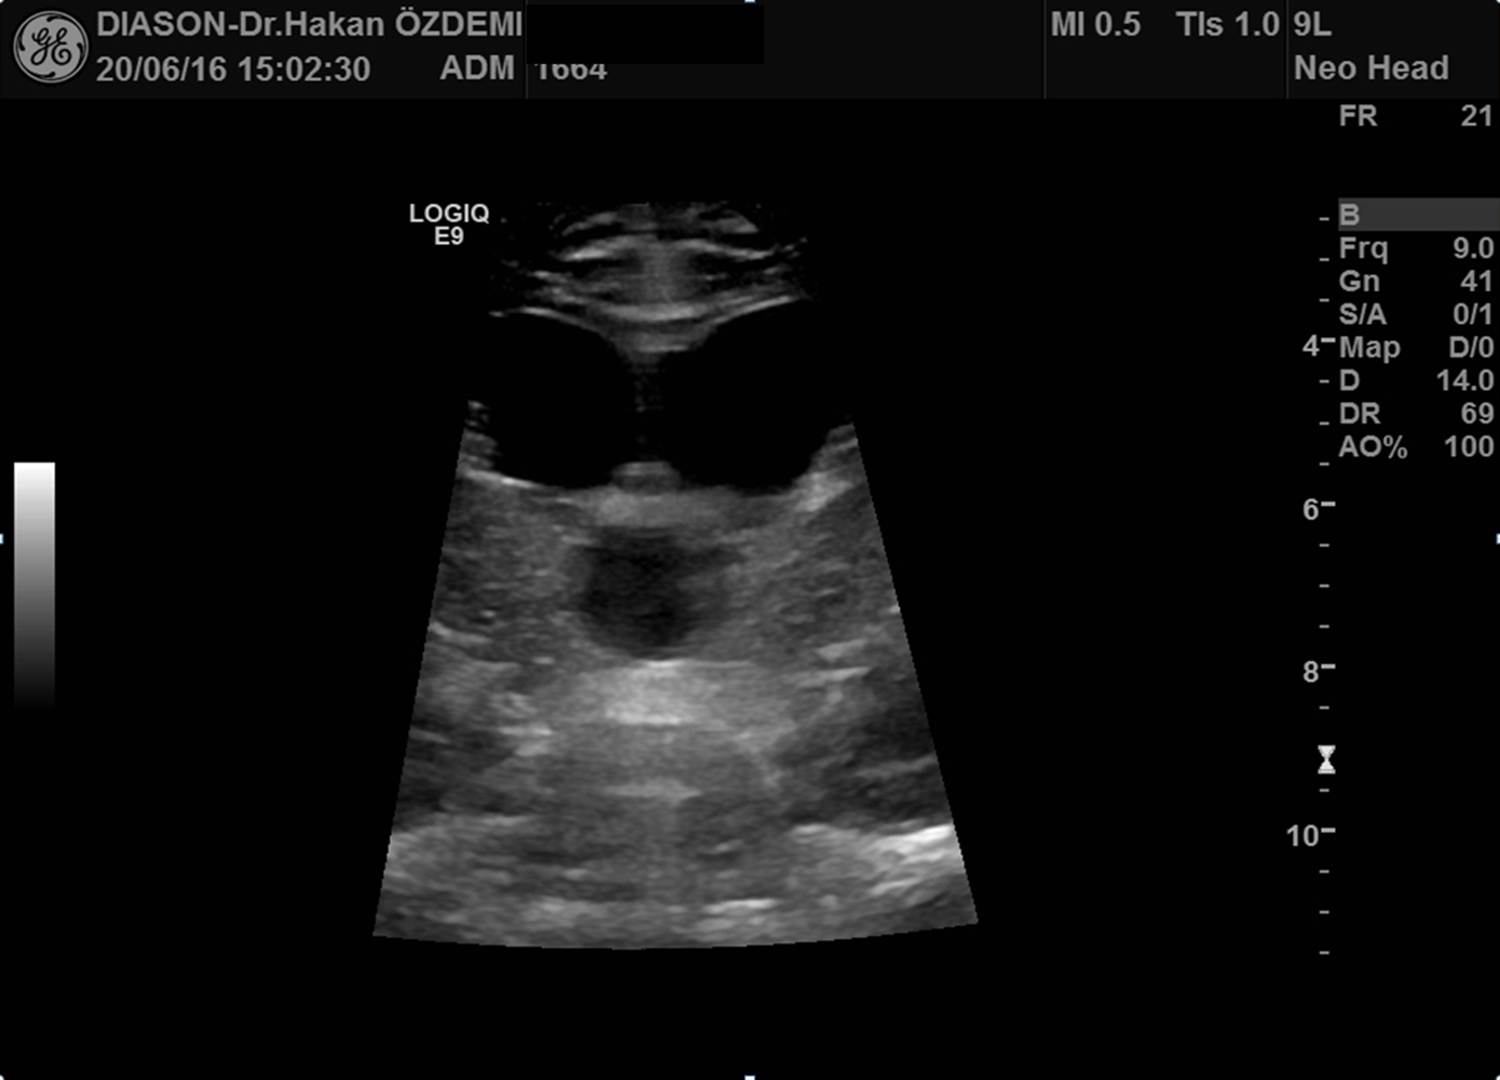

Ultrason, yüksek frekanslı ses dalgaları (ultrases) kullanılarak vücut içindeki organların ve diğer yapıların görüntülenmesi yöntemidir. Ultrasonda kullanılan ses dalgaları insan kulağının işitemeyeceği kadar yüksek frekansa sahiptir. Ultrason görüntülemede iyonizan radyasyon (X-ışınları) kullanılmadığı için bilinen zararlı etkisi bulunmamaktadır.

Ultrason cihazı, içerisinde bilgisayar ve elektronik aletlerin bulunduğu bir konsol, görüntülerin izlendiği bir ekran ve vücudu taramada kullanılan prob (transdüser) dan oluşmaktadır.

İnceleme sırasında prob ile vücut yüzeyi arasındaki temas jel aracılığı ile sağlanmaktadır. İncelenen bölgeye jel sürülmesinin nedenleri yüzeyin kayganlaştırılmasını sağlamak ve probun hava ile temasını önlemektir. Ultrason görüntülemenin temeli, yarasalar ve gemilerin kullandığı "sonar" ile aynıdır. Ses dalgaları vücuttan geçerken oluşan yansımalar, objenin uzaklığı, büyüklüğü, şekli ve yoğunluğunu tanımlamada kullanılır.

Ultrason probları, hem ses üreteci (hoparlör) hem de ses alıcısı (mikrofon) olarak çalışır. Prob cilde bastırıldığında vücut içine yüksek frekanslı, duyulamayan ses dalgaları yollar. Ses dalgaları vücuttaki doku ve sıvılardan yansıdıkça, prob yansıyan dalgaların özelliğini ve şiddetini kaydeder. Doppler ultrason da ise, prob ses dalgalarının yönü ve şiddetindeki küçük değişiklikleri kaydeder.

Bu yansımalar prob içinde bulunan özel kristaller aracılığıyla elektrik sinyallerine dönüştürülür. Daha sonra cihazın içinde yeralan bilgisayar aracılığı ile bu sinyallerden ekranda izlenen gerçek zamanlı görüntüler oluşturulur.